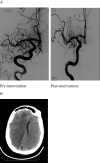

Background and purpose: Coronavirus disease 2019 (COVID-19) is a global pandemic that causes flu-like symptoms. There is a growing body of evidence suggesting that both the central and peripheral nervous systems can be affected by SARS-CoV-2, including stroke. We present three cases of arterial ischemic strokes and one venous infarction from a cerebral venous sinus thrombosis in the setting of COVID-19 infection who otherwise had low risk factors for stroke.

Results: There were 3 cases of arterial ischemic strokes and 1 case of venous stroke: 3 males and 1 female. The mean age was 55 (48-70) years. All arterial strokes presented with large vessel occlusions and had mechanical thrombectomy performed. Two cases presented with stroke despite being on full anticoagulation.